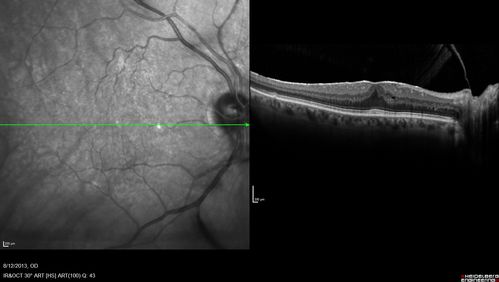

Macular Hole Left Eye - progression from VMT - Stage II macular hole - Spontaneously Closed Macular Hole

Macular Hole from Vitreomacular traction to Stage II hole to Spontaneously Closed Hole